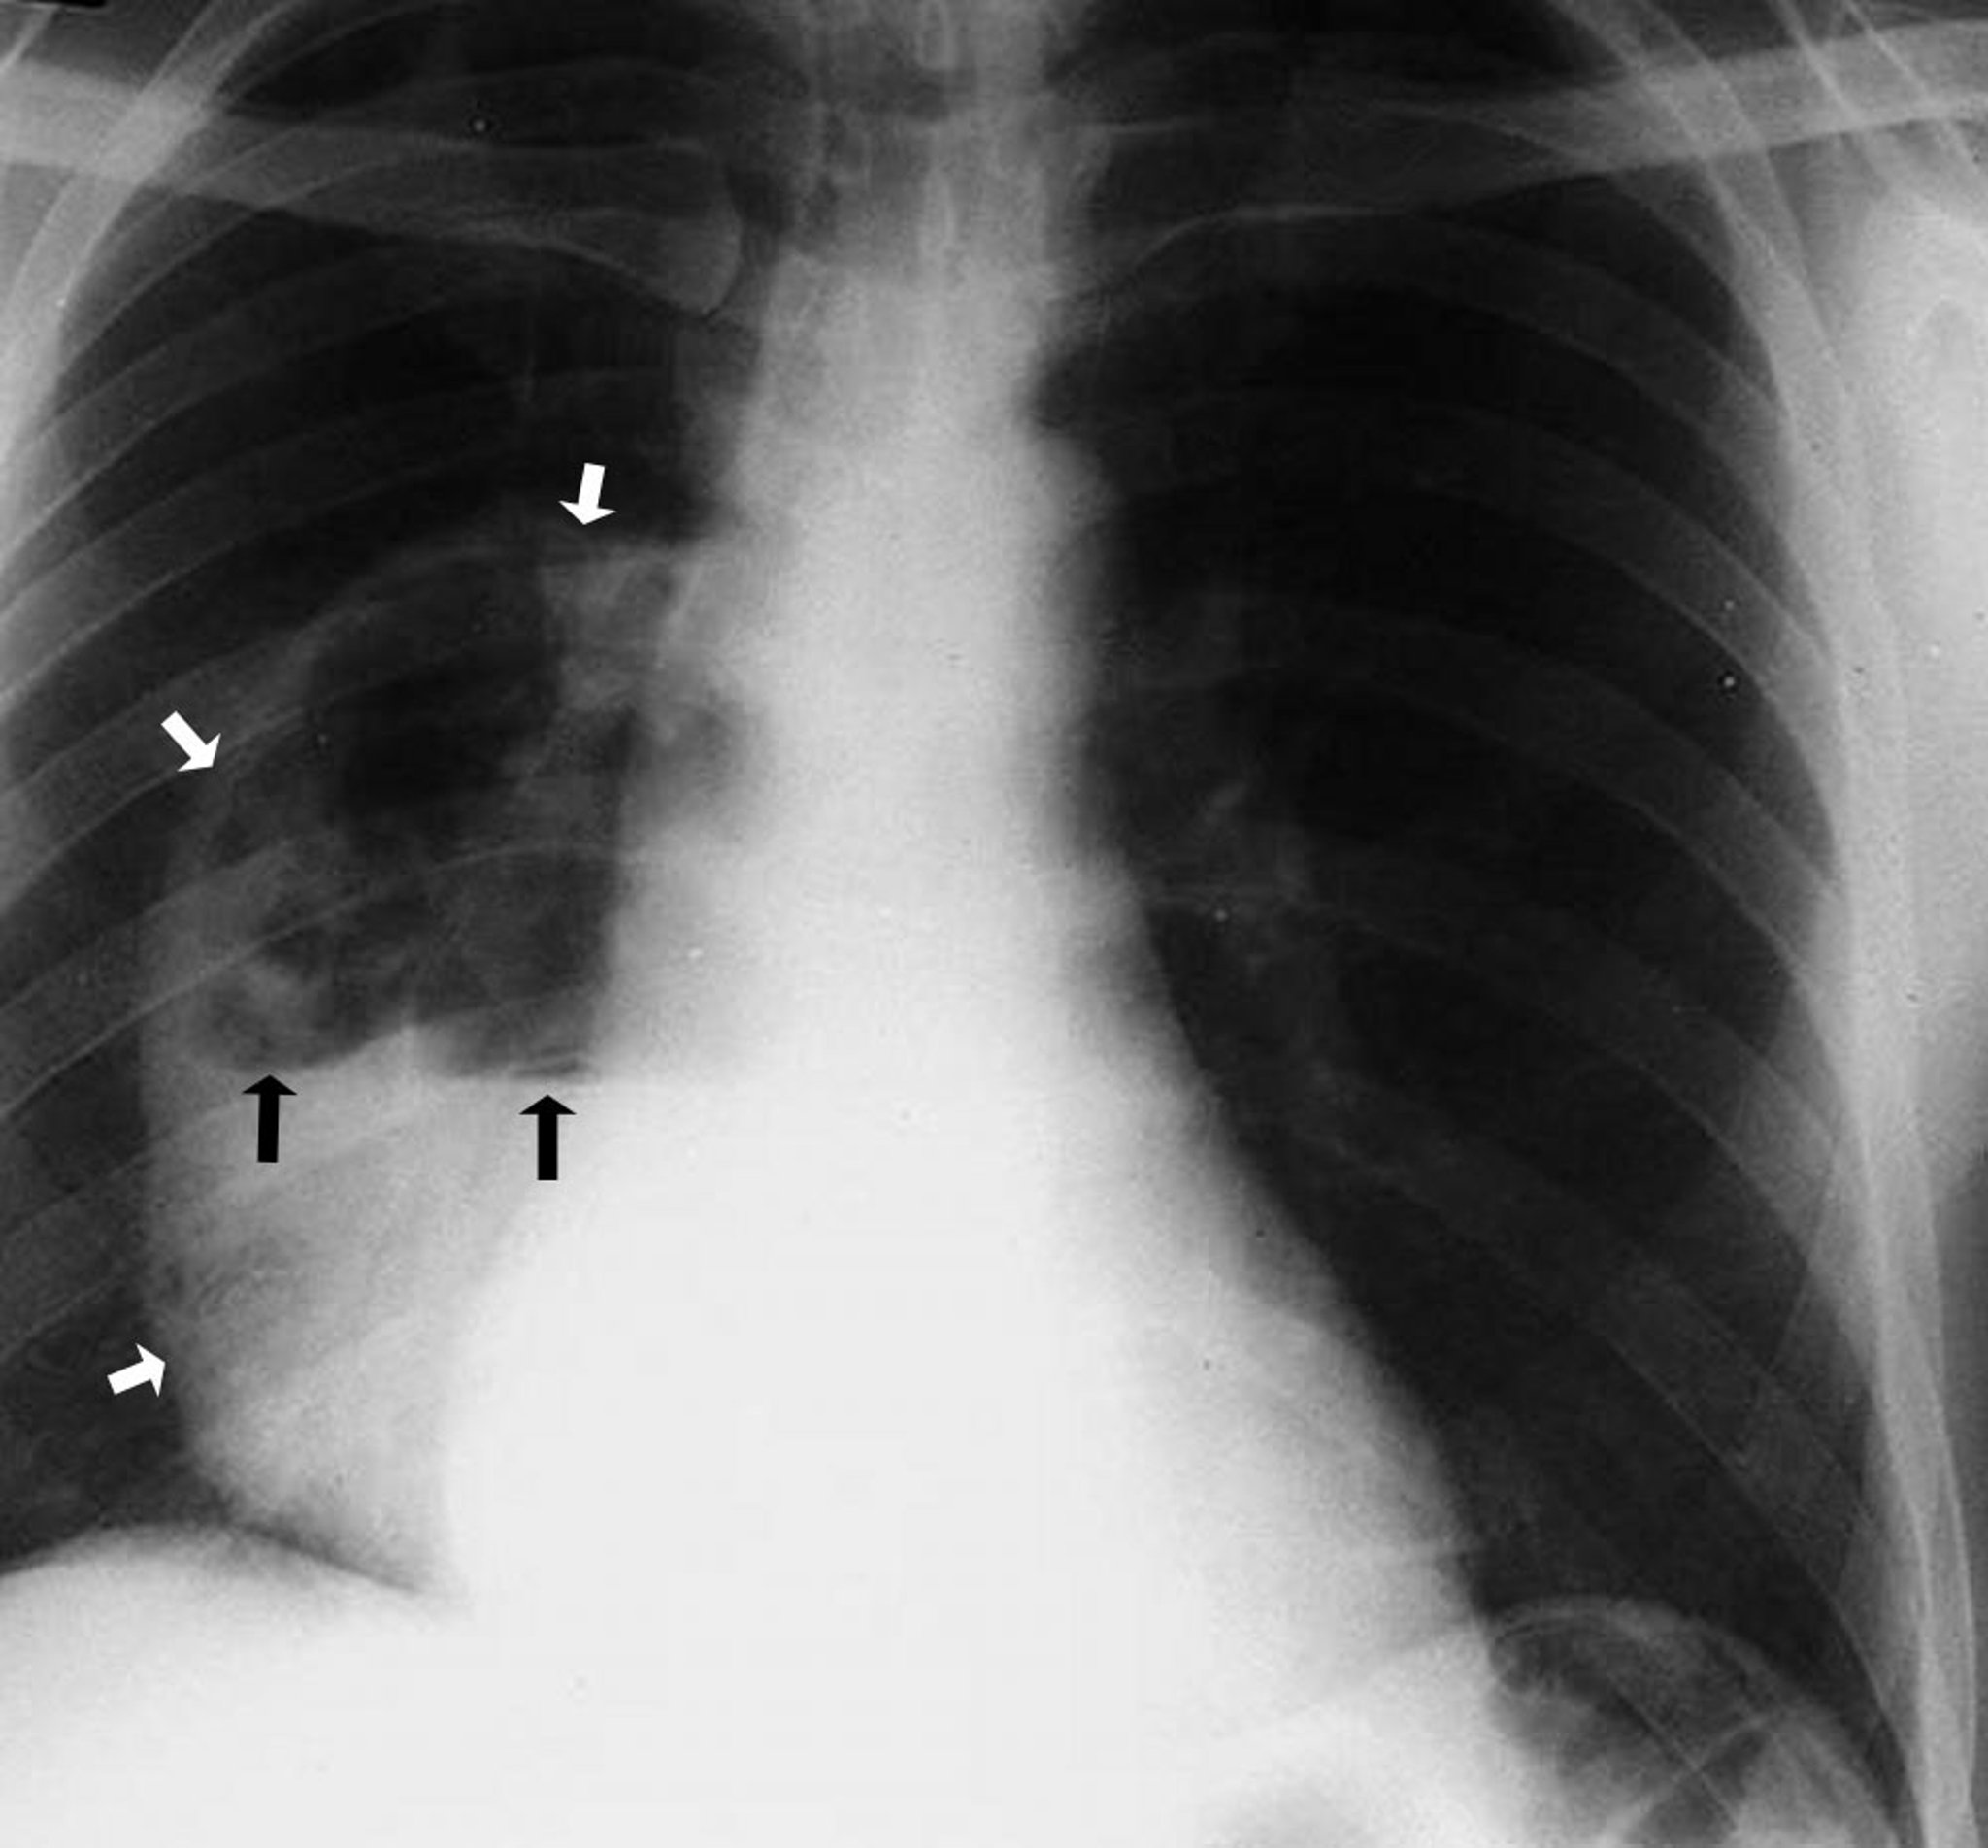

Lung Abscess (Radiograph)

This photo shows a large right lower lobe abscess demonstrating a cavity that contains an air-fluid level. The white arrows point out the boundary of the abscess showing the walls separated from the lung parenchyma. The black arrows demarcate the level where the air above and fluid below meet.

By permission of the publisher. From Leaf H. In Atlas of Infectious Diseases: Pleuropulmonary and Bronchial Infections. Edited by GL Mandell (series editor) and MS Simberkoff. Philadelphia, Current Medicine, 1996.